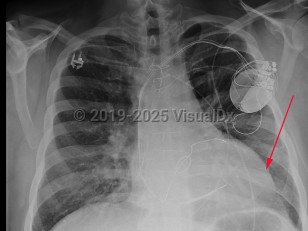

Patients usually present with symptoms of heart failure including dyspnea, edema, orthopnea, and weight gain. Physical examination may reveal signs of acute left ventricular failure, such as S3 gallop, systolic murmur consistent with mitral regurgitation, pleural effusions, jugular venous distension, and/or peripheral edema.